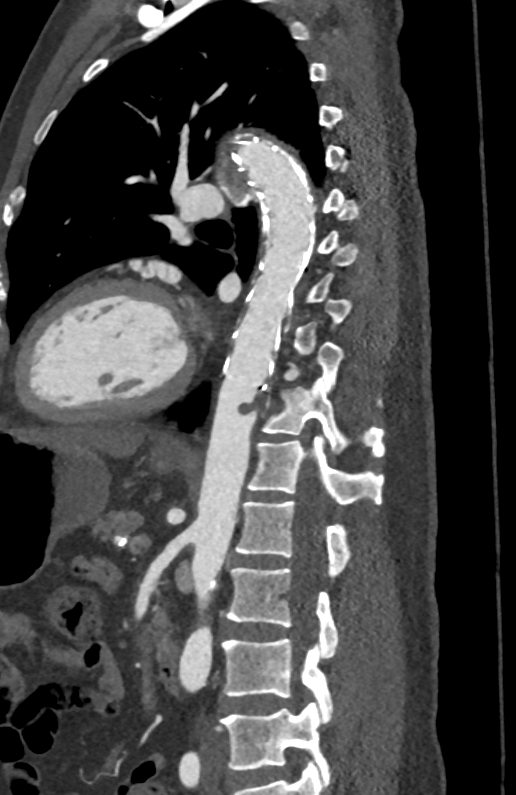

联系卒中中心医生会诊并收住院治疗,经专科查体发现患者T6脊髓节段水平以下痛温觉、触觉

明显减退,双侧巴氏征阳性。

这是一个典型的脊髓横贯性损害体征,提示病灶位于胸髓。加做胸椎+腰椎磁共振平扫

,仅发现广泛的退行性变和椎间盘突出,未见明确的脊髓肿胀、异常信号或占位性病变。(见图3、图4)

图3

图4